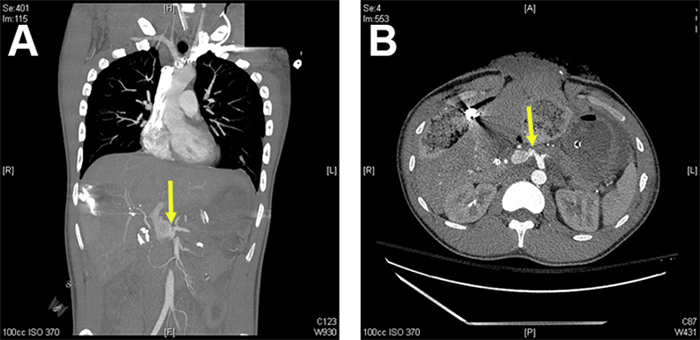

Since the patient was not showing signs of heart failure or portal hypertension, treatment of the arterioportal fistula was delayed until he was off ECMO. Before closure of the patient's abdomen, interventional radiology performed a celiac arteriogram that redemonstrated the fistula between the proximal left hepatic artery and a dilated main portal vein (Figure 2). The hepatic artery had a low bifurcation, with the left hepatic artery originating quite proximally at the level of the main portal vein injury. Due to the fistula being only 1‒2 mm distal to the origin of the left hepatic artery, it was not amendable to arterial stent-graft placement.

Figure 2. Celiac angiogram showing arterioportal fistula. Published with Permission